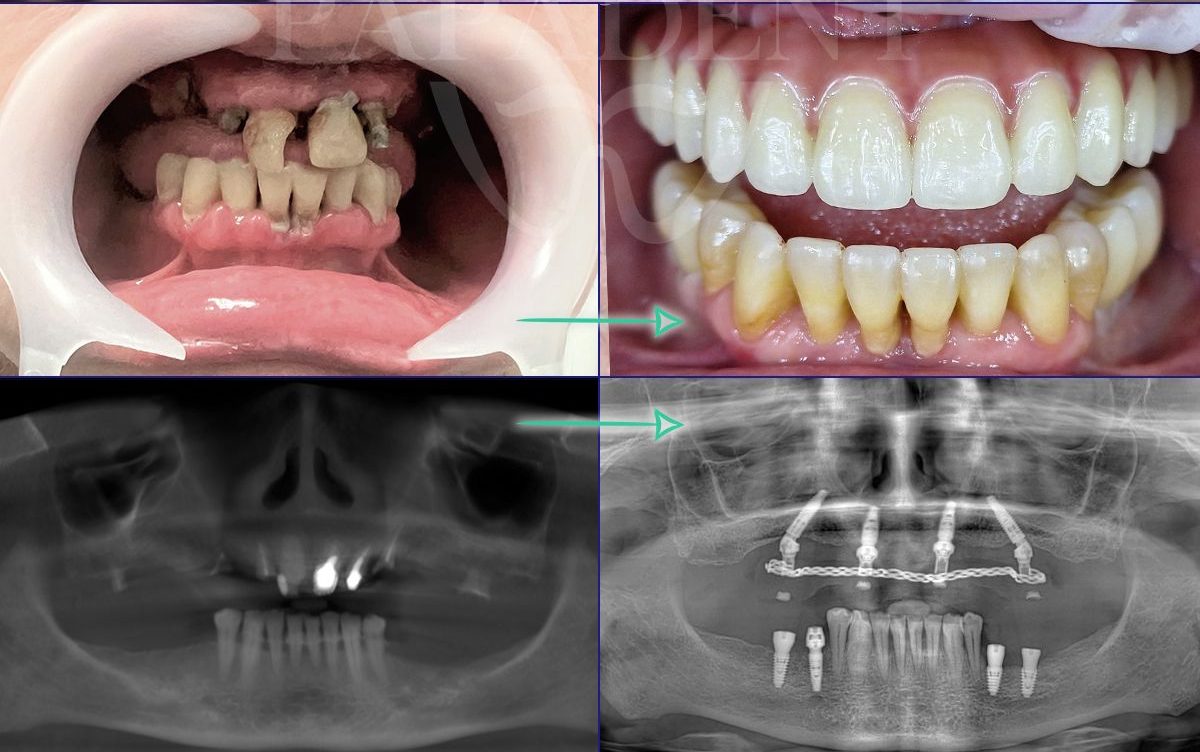

Gyd. Tomo Stumbrio komentaras: pacientas turėjo beveik visus dantis, bet dėl nepakankamai kontroliuojamos periodonto ligos dauguma dantų buvo netekę 70% kaulo, judėjo ir pūliavo. Konservatyvus gydymas buvo įmanomas, bet ilgas kelias iki to ir prognuozuojamas rezultatas netenkino paciento. Buvo pašalinti 26 dantys ir įsriegta 10 implantų. Po 48 val. uždėti laikini protezai, kurie po 6 mėn. pakeisti nuolatiniais protezais iš cirkonio ant titaninio karkaso.